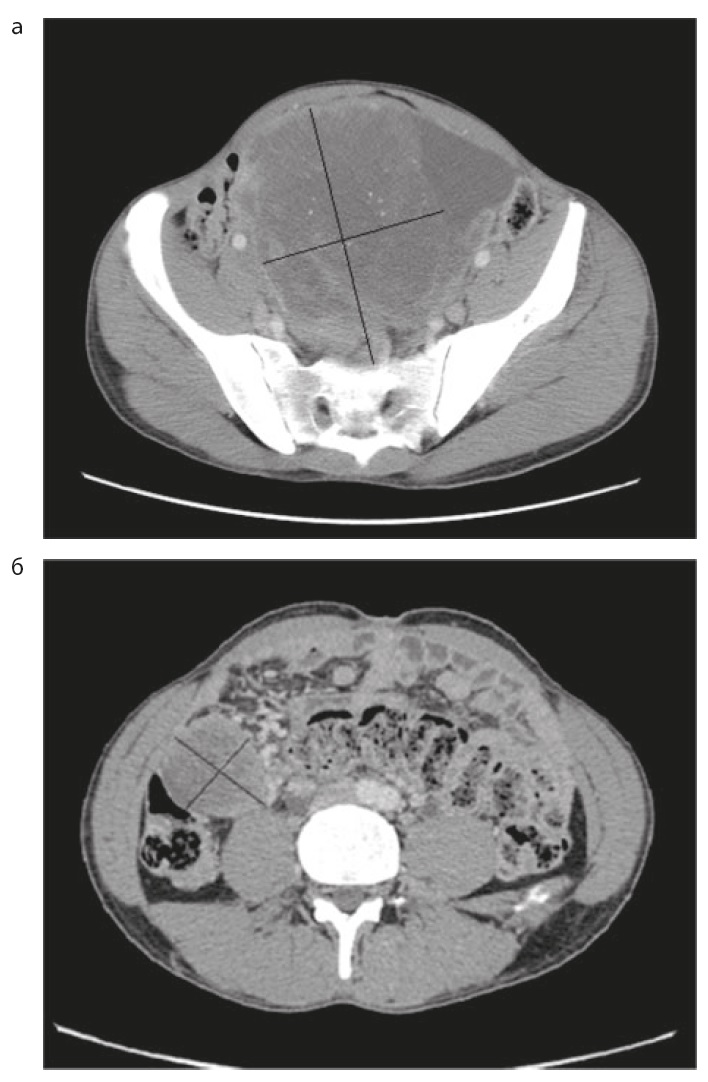

Лучевые и инструментальные методы диагностики, такие как компьютерная томография (КТ), магнитно-резонансная томография, лапароскопия, имеют решающее значение в определении степени распространенности опухоли, при этом необходимо учитывать биологические особенности опухоли (морфологический тип), которые влияют на характер ее роста. При СФО и ДМКО картина КТ характеризуется наличием изолированных узловых образований в любом отделе брюшной полости, которые также могут сопровождаться поражением большого сальника, наличием асцита, увеличением забрюшинных лимфоузлов, возможно отдаленное метастазирование в легкие и кости (рис. 1, 2) [13].

Рис. 2. Солитарная фиброзная опухоль [8].

Fig. 2. Desmoplastic small round cell tumor [8].

В целом находки при КТ неспецифичны, однако имеют важное значение при выборе тактики лечения и определения возможного объема операции.